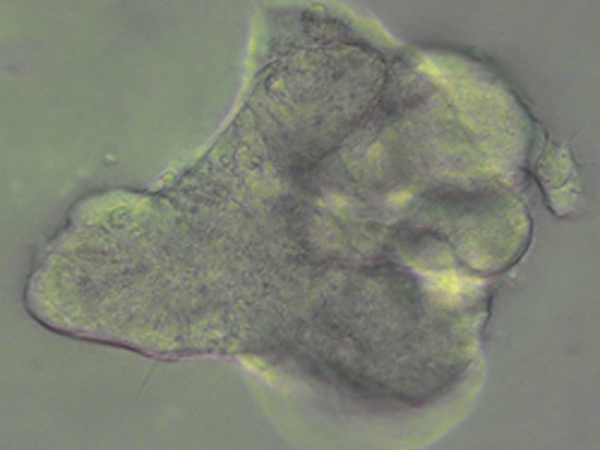

Từ những tế bào da của bệnh nhân xơ nang phổi, các nhà khoa học trường địa học Cambridge đã chế tạo thành công cụm tế bào mô phỏng các chức năng của lá phổi bị bệnh. Kết quả của nghiên cứu này sẽ là tiền đề giúp giải quyết vấn đề sức khỏe của bệnh nhân mắc bệnh xơ nang phổi. Bằng cách quan sát lá phổi mini này hoạt động, các bác sĩ sẽ có góc nhìn chính xác hơn về diễn biến của bệnh và tìm ra loại thuốc đặc trị trên một quy mô nghiên cứu lớn hơn.

Nghiên cứu được thực hiện đối với một chúng xơ nang phổi điển hình (chiếm 75%) gây nên bởi một đột biến trong gen CFTR, thường gọi là là đột biến delta-F508. Các tế bào được lấy từ da người bệnh sẽ được tái lập trình tới trạng thái đa năng cảm ứng (induced pluripotent state - ở trạng thái này các tế bào có thể phát triển thành bất cứ loại tế bào nào trong cơ thể) và trở thành các tế bào đa năng cảm ứng (iPS - induced pluripotent stem). Sử dụng các tế bào loại này, các nhà khoa học tái tạo lại sự phát triển của phôi phổi trong phòng thí nghiệm bằng cách kích hoạt một quá trình hình thành phôi dạ (gastrulation) theo đó các tế bào này sẽ tạo thành các lớp bào riêng biệt bao gồm đầu tiên là các nội bì sau đó là ruột trước (foregut), từ đó hình thành nên lá phổi. Tiếp sau đó, những tế bào này sẽ tiếp tục được kích thích để phát triển thành mô đường hô hấp ngoại biên (the distal airway), phần của phổi chịu trách nhiệm luân chuyển khí và thường liên quan đến các bệnh như xơ nang phổi hay một số dạng ung thư phổi.